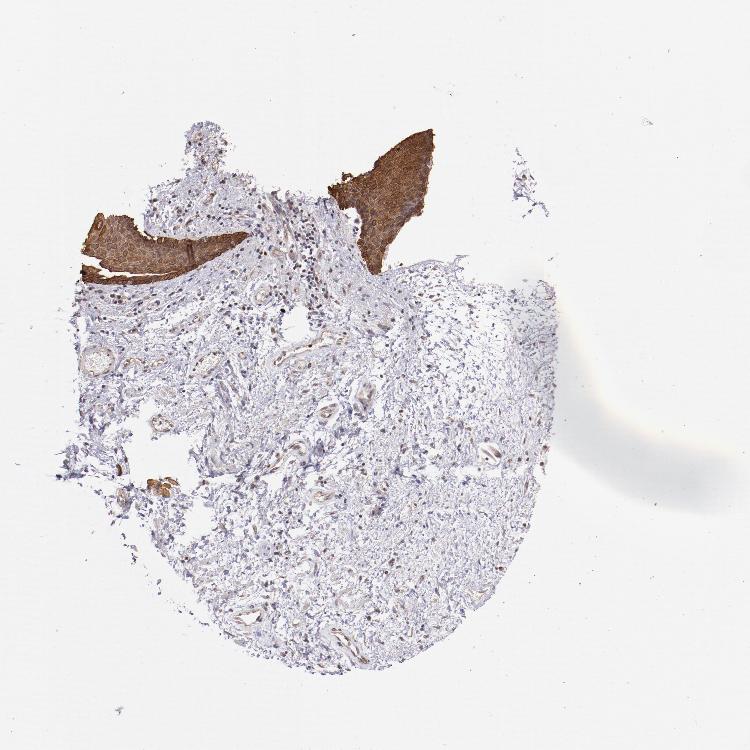

SKIN 1 - Antibody stainingi

Antibody staining in the annotated cell types in the current human tissue is reported as not detected, low, medium, or high, based on conventional immunohistochemistry profiling in selected tissues. This score is based on the combination of the staining intensity and fraction of stained cells.

Each image is clickable and will lead to virtual microscopy that enables deeper exploration of all samples and also displays staining intensity scores, fraction scores and subcellular localization as well as patient and tissue information for each sample.

Antibody HPA001755Antibody CAB005172

Langerhans Not detectedMedium

Fibroblasts MediumMedium

Keratinocytes MediumMedium

Melanocytes MediumMedium